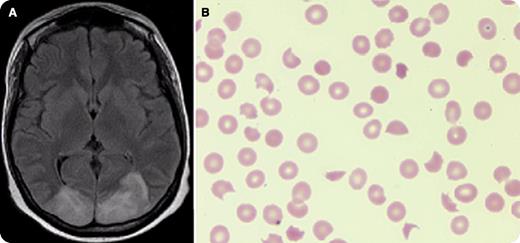

A 25-year-old woman with FLT3-ITD positive acute myeloid leukemia underwent cord blood transplantation with fludarabine, cyclophosphamide, and total body irradiation conditioning. Despite prophylaxis with mycophenolate and tacrolimus, she suffered from grade 4 gastrointestinal graft-versus-host disease that was managed with rabbit antithymoglobulin and extracorporeal photopheresis. She developed posterior reversible encephalopathy syndrome (PRES) manifesting with encephalopathy, seizures, and consistent brain magnetic resonance imaging (panel A) and thrombotic microangiopathic anemia (TMA) with schistocytes on peripheral blood smear (panel B), elevated lactate dehydrogenase, low haptoglobin, and normal ADAMTS13. Cessation of tacrolimus and administration of eculizumab led to the resolution of both. Subsequently, she died after complications from cytomegalovirus, Pneumocystis jirovecii, and enterococcus infections.

This case demonstrates the challenges and unique pathologies associated with allogeneic transplantation. Calcineurin inhibitors are known to cause PRES and TMA but the relationship between these pathologies is unknown. Our case highlights that after diagnosis of either, evaluation for the second should be considered.